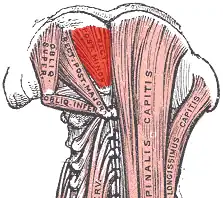

Deep muscles of the back. (rectus capitis posterior minor labeled at top center.) | |